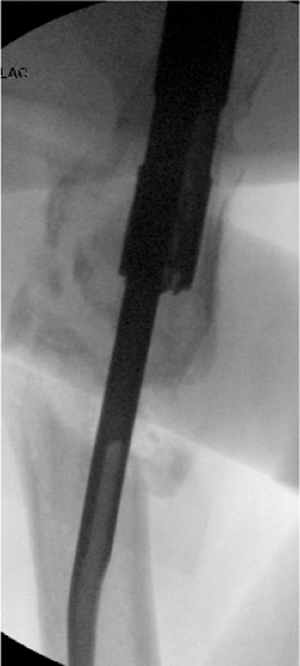

![]() |

Figure 20.6. A,B. Tip-threaded guide pin inserted into piriformis fossa, centered on lateral view.

crucial. Incorrect starting points can lead to angular deformities. For

conventional, reamed, piriformis, intramedullary nailing, the correct

starting point is in the piriformis fossa. However, for reconstruction

nailing, the portal of entry is slightly anterior to the fossa. Because

the femoral neck arises from the anterior portion of the proximal

femur, moving the starting point 3 to 4 mm anteriorly facilitates

proximal screw insertion. A 3.2-mm threaded guide pin is inserted at

the entry site and confirmed by fluoroscopy to be in the midline of the

femur in both AP and lateral views (Fig. 20.6). The entry portal is enlarged with the cannulated reamer over the guide pin (Fig. 20.7).